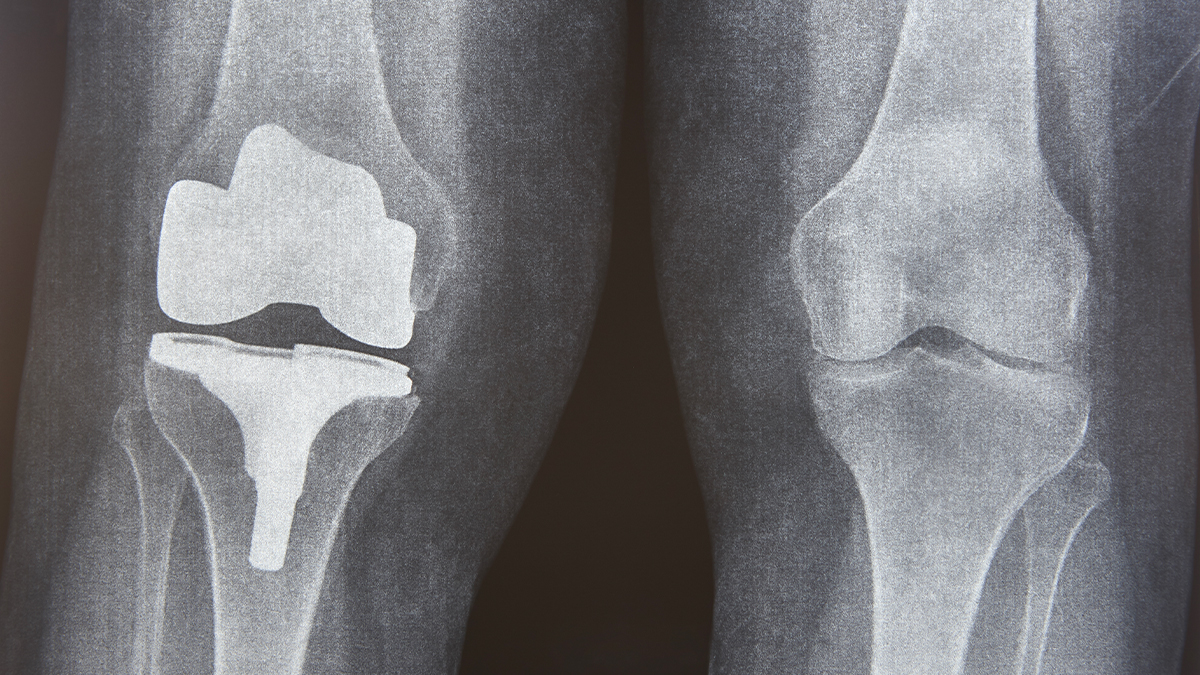

Nová studie zjistila, že pacienti podstupující běžný typ náhrady velkého kloubu mají zvýšené hladiny některých kovů v krvi, mozku a mozkomíšním moku, což vyvolává obavy z možných dlouhodobých nežádoucích neurologických účinků.

Ve Spojených státech se každoročně provede přibližně 790 000 totálních náhrad kolenního kloubu a 544 000 náhrad kyčelního kloubu. Očekává se, že s přibývajícím věkem populace budou tato čísla nadále stoupat.

Pilotní studie NeuroWear, nedávno zveřejněná v odborném časopise JAMA Network Open, porovnávala 103 osob s kloubními implantáty se 108 lidmi bez implantátů. Výsledky ukázaly, že pacienti s implantáty měli vyšší koncentrace kovů v krvi a mozkomíšním moku, což naznačuje, že kovy z implantátů – zejména kobalt – mohou pronikat do centrálního nervového systému.

Hladina kobaltu v mozkomíšním moku byla u skupiny s implantáty zaznamenána na úrovni 0,03 mikrogramu na litr, zatímco u kontrolní skupiny činila 0,02 mikrogramu na litr.

Kromě kobaltu vykazovali pacienti s implantáty zvýšené hladiny chromu, titanu, niobu a zirkonia v krvi, přičemž některé z těchto kovů byly zjištěny i v mozkomíšním moku. Výrazně vyšší koncentrace kovů byly zaznamenány u účastníků s komponenty implantátů obsahujícími slitinu kobaltu, chromu a molybdenu.

Titan a slitina kobaltu a chromu patří v současnosti k nejčastěji používaným kovům při výrobě kloubních náhrad. Slitiny kobaltu, chromu a molybdenu jsou ceněny pro svou pevnost, odolnost a rezistenci vůči korozi, což z nich činí oblíbený materiál pro kovové komponenty náhrad kloubů – zejména kyčelních a kolenních. Tyto kloubní náhrady však mohou v některých svých částech obsahovat i keramické materiály, například oxid hlinitý nebo oxid zirkoničitý, které zajišťují vyšší odolnost vůči opotřebení a lepší biokompatibilitu, zejména u kyčelních implantátů.